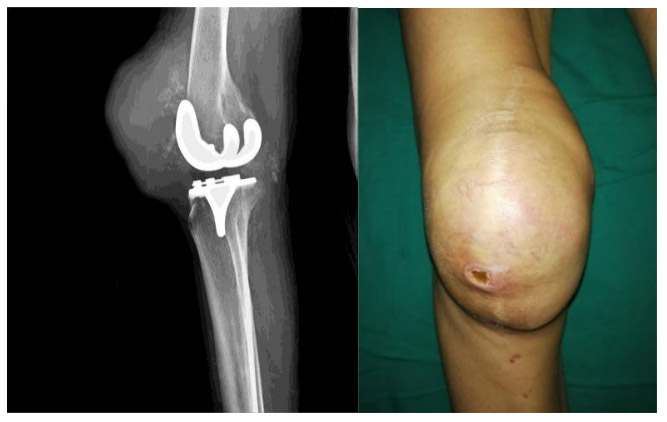

CASE 46: Hemangiopericytoma metastasis to the kneecap (patella)

Before the surgery: X-ray shows significant damage to the kneecap and the presence of a prosthesis. Clinically, there is swelling in the front of the knee.